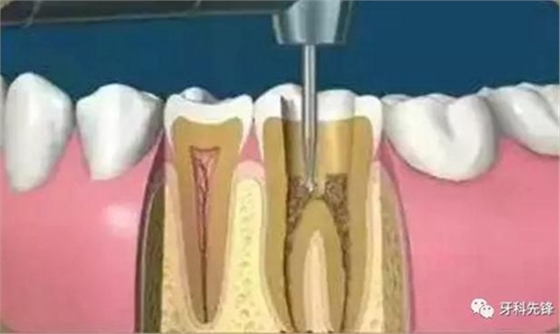

4、根管預(yù)備

根管清理成形的目的是去凈根管壁上的感染物,通過根管器械的切削作用去除感染的牙本質(zhì)并清理根管壁細(xì)菌以利于根管充填。